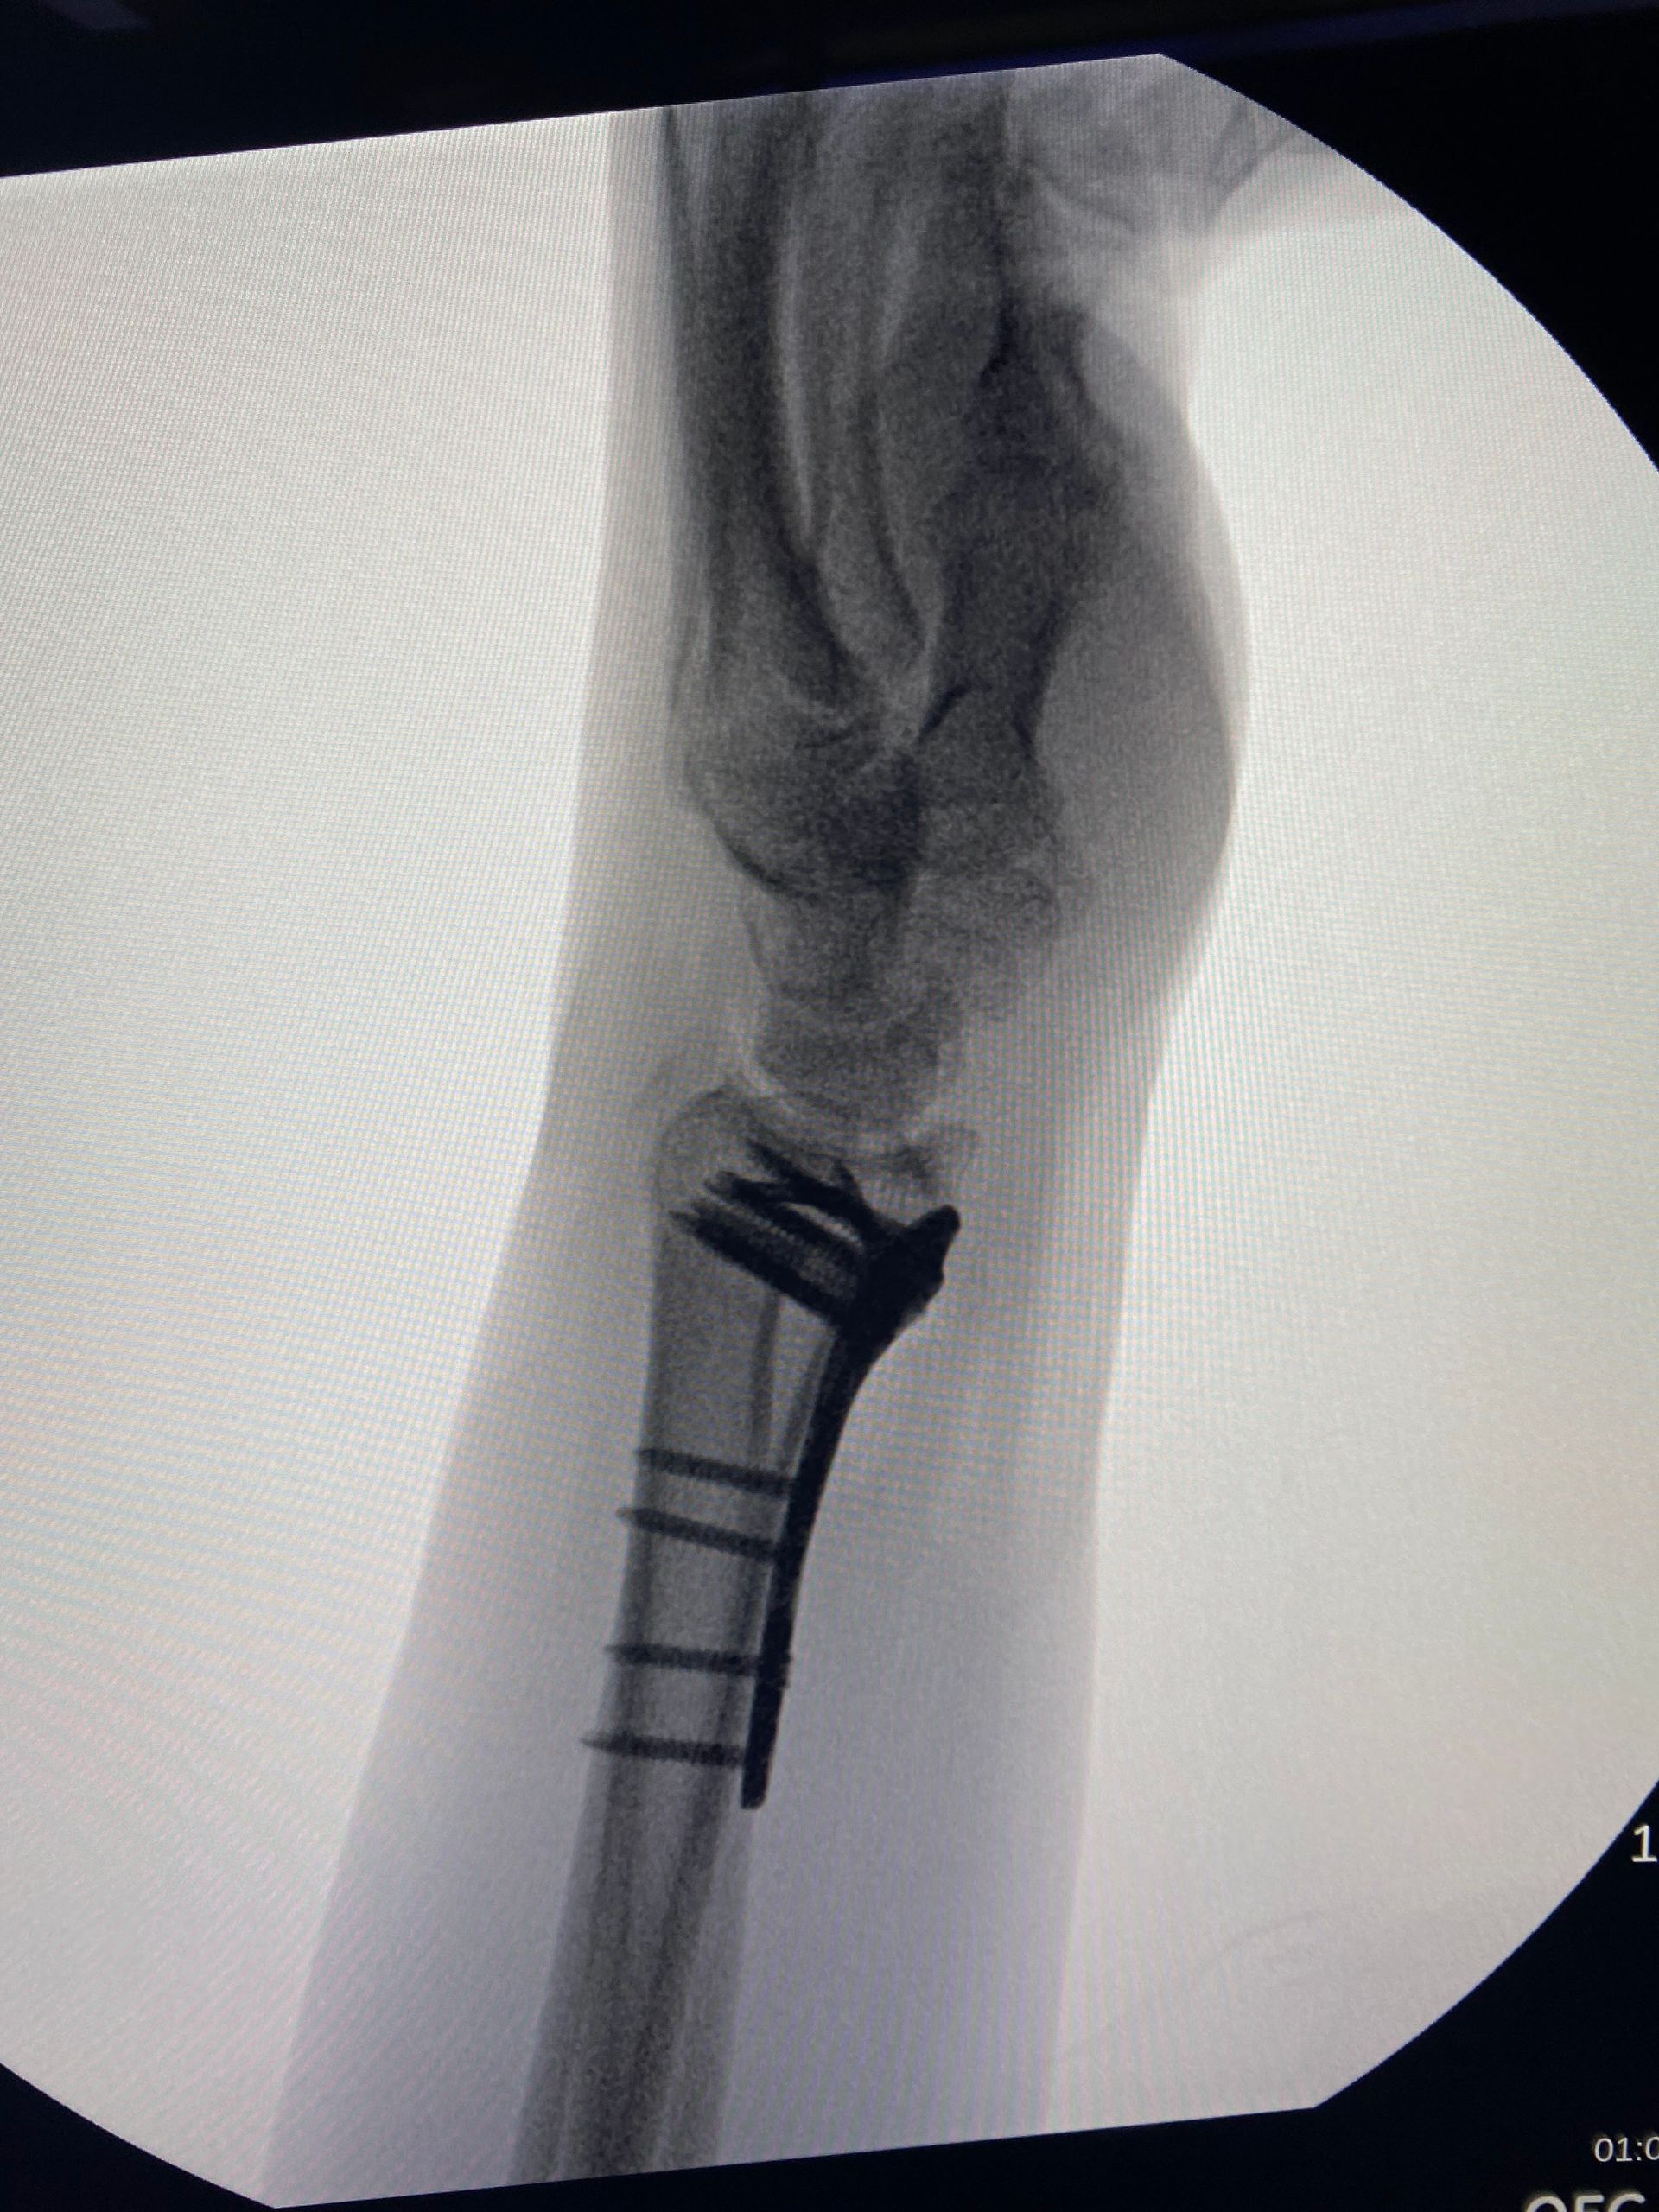

2) Redução aberta e osteossíntese

- Placa volar / dorsal

A

placa volar se tornou a forma padrão de tratamento de maioria das fraturas distais de rádio, podendo ser utilizada tanto para fraturas articulares quanto não articulares. Quando bem manuseada, possui a capacidade de manter a redução de fraturas com desvio inicial dorsal, volar ou mesmo com deslocamento radial do fragmento distal.

A placa e os parafusos bloqueados possuem diversas vantagens:

- Redução anatômica do córtex volar facilitar a restauração do comprimento radial, inclinação e tilt volar;

- Ao evitar dissecção de fragmentos dorsais, há uma tendência de preservar o suprimento vascular dos fragmentos dorsais;

- Quando utilizada uma placa bloqueada, há menor necessidade de uso de enxerto ósseo;